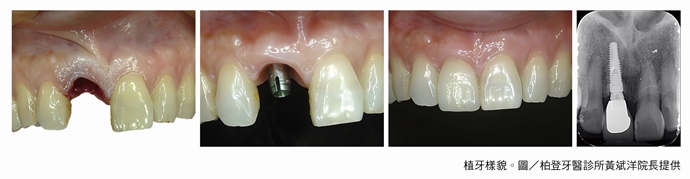

◆作法:黃斌洋院長表示,植牙是一種侵入性治療,能重建牙根及牙冠。在齒槽骨內安置一個替代的牙根(植體),等待植體與周圍齒槽骨緊密結合後,再製作牙冠,將假牙建立在人工牙根上方,就能有全新的牙齒,但植牙並非人人適合,術前必須做完整的評估。

植牙樣貌

◆植牙8步驟

①術前診斷、評估及檢查:專業的牙醫師會先檢查患者口腔現狀,判斷是否可植牙。若有心血管疾病、骨質疏鬆、腎臟病等植牙風險,需經醫師評估後方能進行。確定身體可接受植牙後,會使用包含X光片、3D口內數位掃描機、3D電腦斷層等精密儀器檢查,確認牙齒現狀、牙齒強度、齒槽骨狀態,做好周全準備。

②術前補骨治療:若有齒槽骨萎縮、牙周病、蛀牙等病況,需先治療好才能植牙。若齒槽骨萎縮,需額外進行補骨粉、上骨膜等治療,增加骨質強度、提高齒槽骨穩固度。若有蛀 牙、牙周病,都需先治療好,才能為植牙打好地基,提高植牙穩定性及成功率。

③進行人工植體(牙根)手術:手術前,醫師會使用電腦斷層充分了解齒槽骨結構,讓人工牙根避開神經與血管。植體手術是利用手術刀或水雷射將齒槽骨組織及骨膜切開,並在植牙區域鑽洞後將植體鎖入齒槽骨,最後再將傷口縫合。傳統植入人工牙根手術需花費30~60分鐘,微創植牙可縮短15~30分鐘,採局部麻醉,也可選擇舒眠植牙方式,睡一覺後已植好牙根。

④ 等待骨整合:術後需有等待人工牙根和齒槽骨穩定結合的時間,也就是骨整合。骨整合所 需時間會依個人原始骨質狀況有差異。除非原始骨質就非常堅硬,否則一般建議至少等待3個月以上較安全。牙齒能夠正常受力後,才能安裝人工牙冠。

⑤安裝臨時假牙:待骨質穩定且牙齦成形後,牙醫師會安裝臨時假牙,目的是幫助牙肉塑型,有正確的生長弧度,確保後續生長位置正確,並讓患者提早適應日後的咬合。

⑥挑選牙冠材質:手術後2~4週後,需依照硬度與人體相容性機能挑選人工牙冠,有金屬牙冠、金屬外包陶瓷、全瓷冠等材質,可依照硬度、人體相容性、美觀度與價格進行挑選。

⑦安裝正式假牙:完成以上步驟後,需印牙模,交由專業牙技師製作正式假牙冠,等待人工牙根完成骨整合後,醫師就會在穩固地基上安裝正式假牙。

⑧定期回診追蹤:植牙療程結束後需定期回診,通常每3個月回診一次,以確保口腔健康及延長假牙使用壽命。